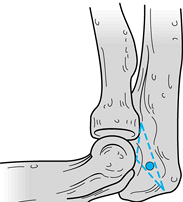

Locate the direct lateral portal among

spot of the elbow (Fig. 82.2). This is a safe

capsule (Fig. 82.3).

Figure 82.2.

The direct lateral portal is located amid the lateral epicondyle,

olecranon tip, and radial head. (From Andrews JR, Carson WG.

Arthroscopy of the Elbow. Arthroscopy 1985;1:97.)